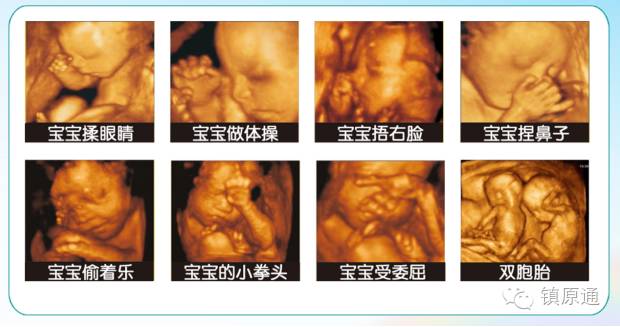

是立体动态显示的彩色多普勒超声诊断仪,可以进行胎儿头面部立体成像,可显示眼、鼻、口、下颌等态势,协助医生直接对胎儿先天畸形进行诊断,价格比普通彩超价格贵。

四维彩超能够对胎儿进行动态、立体超声检查,显示胎儿的面部、各器官的发育情况,甚至胎儿在母体里的态势也可以视察到;对胎儿畸形,如唇裂、腭裂、骨骼发育异常等能早期诊断。另外还能制作成光盘,让宝宝拥有最完整的0岁相册,留下永久的记忆。

过去使用的B超设备只能检查胎儿的一些生理指标,而四维彩超还能对胎儿的体表进行检查,如唇裂,脊柱裂,大脑、肾、心脏、骨骼发育不良等情况,以便尽早的进行治疗,生个聪明健康的小宝宝。四维彩超能进行宫内写真,让准妈妈看到宫内宝宝的一举一动,亲身体会到宝宝的笑容相貌!而且四维彩超可以把宫内四维彩超宝宝的动态刻录成dvd作为宝宝的0岁写真!永久留念!